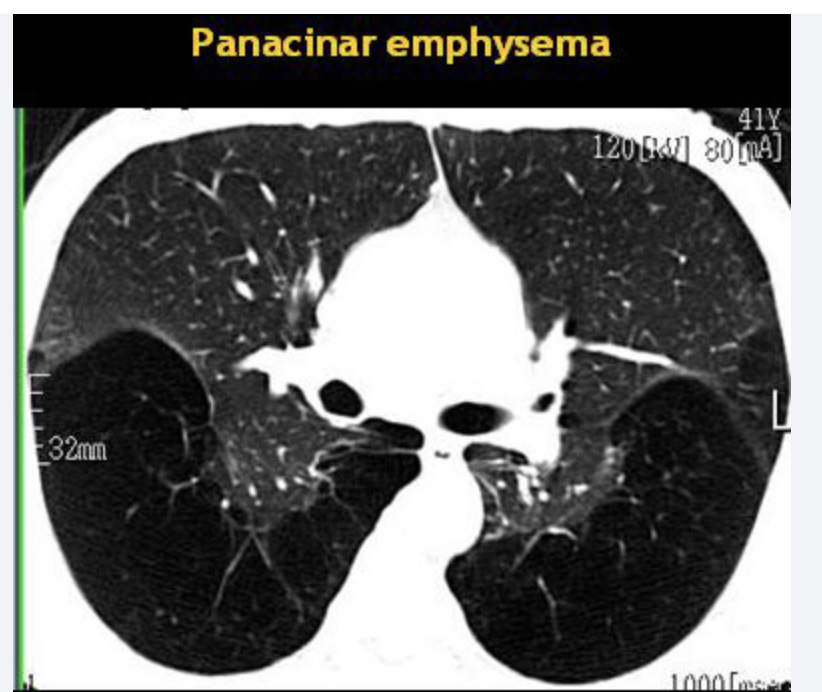

Que es el enfisema

consiste en la dilatación del acino (vía aérea distal a un bron- quíolo terminal) y destrucción de la pared alveolar

Que tipo de enfisema se asocia a deficiencia de alfa 1 antitripsina

A

Tipos de enfisema